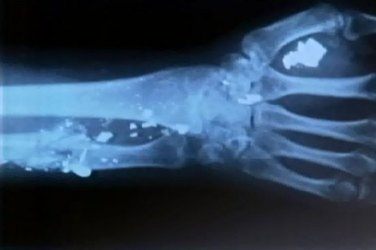

Um pintor luta há oito meses para fazer uma cirurgia e retirar balas alojada na mão e nas costas. O rapaz foi baleado durante um assalto.